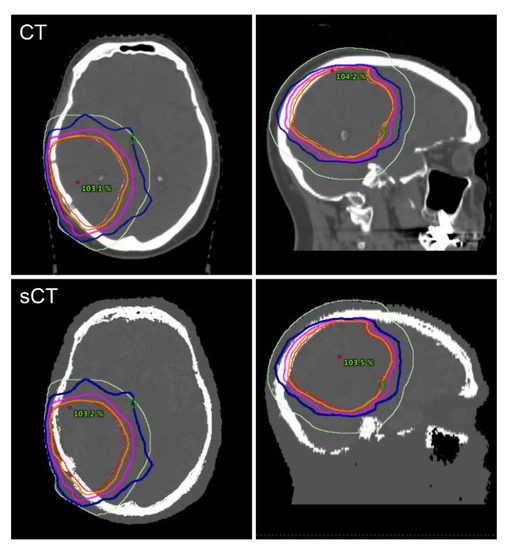

3.2. Dosimetric Comparison